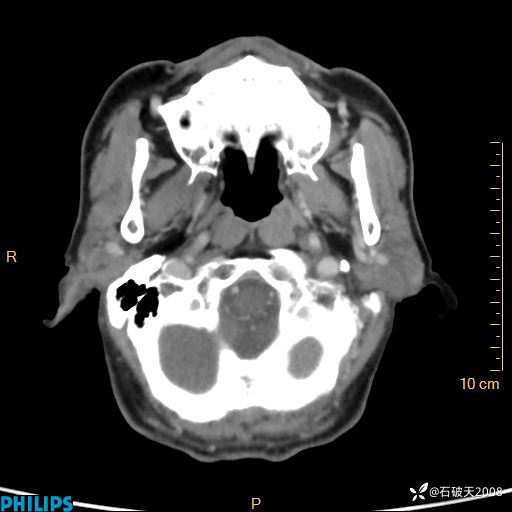

平扫